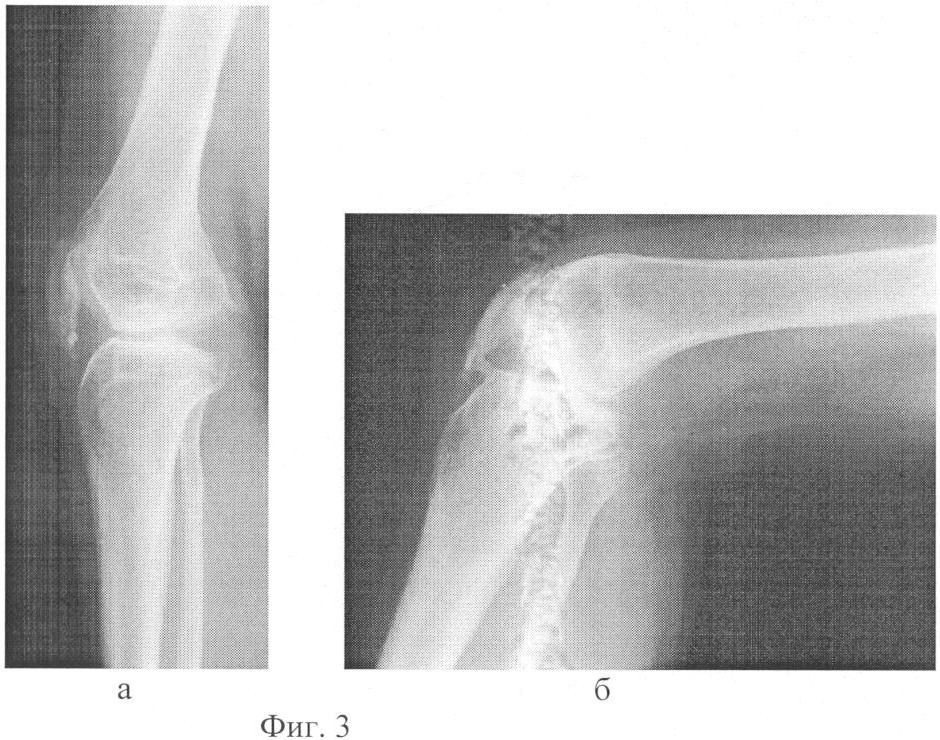

фиг.3 (а, б) – рентгенограммы коленного сустава после лечения: а – в положении разгибания; б – в положении сгибания.

На контрольном осмотре через 6 месяцев больная ходит с полной нагрузкой на оперированную конечность без дополнительных средств опоры, движения в коленном суставе в пределах 165-90°, безболезненны (фиг.3а, б).